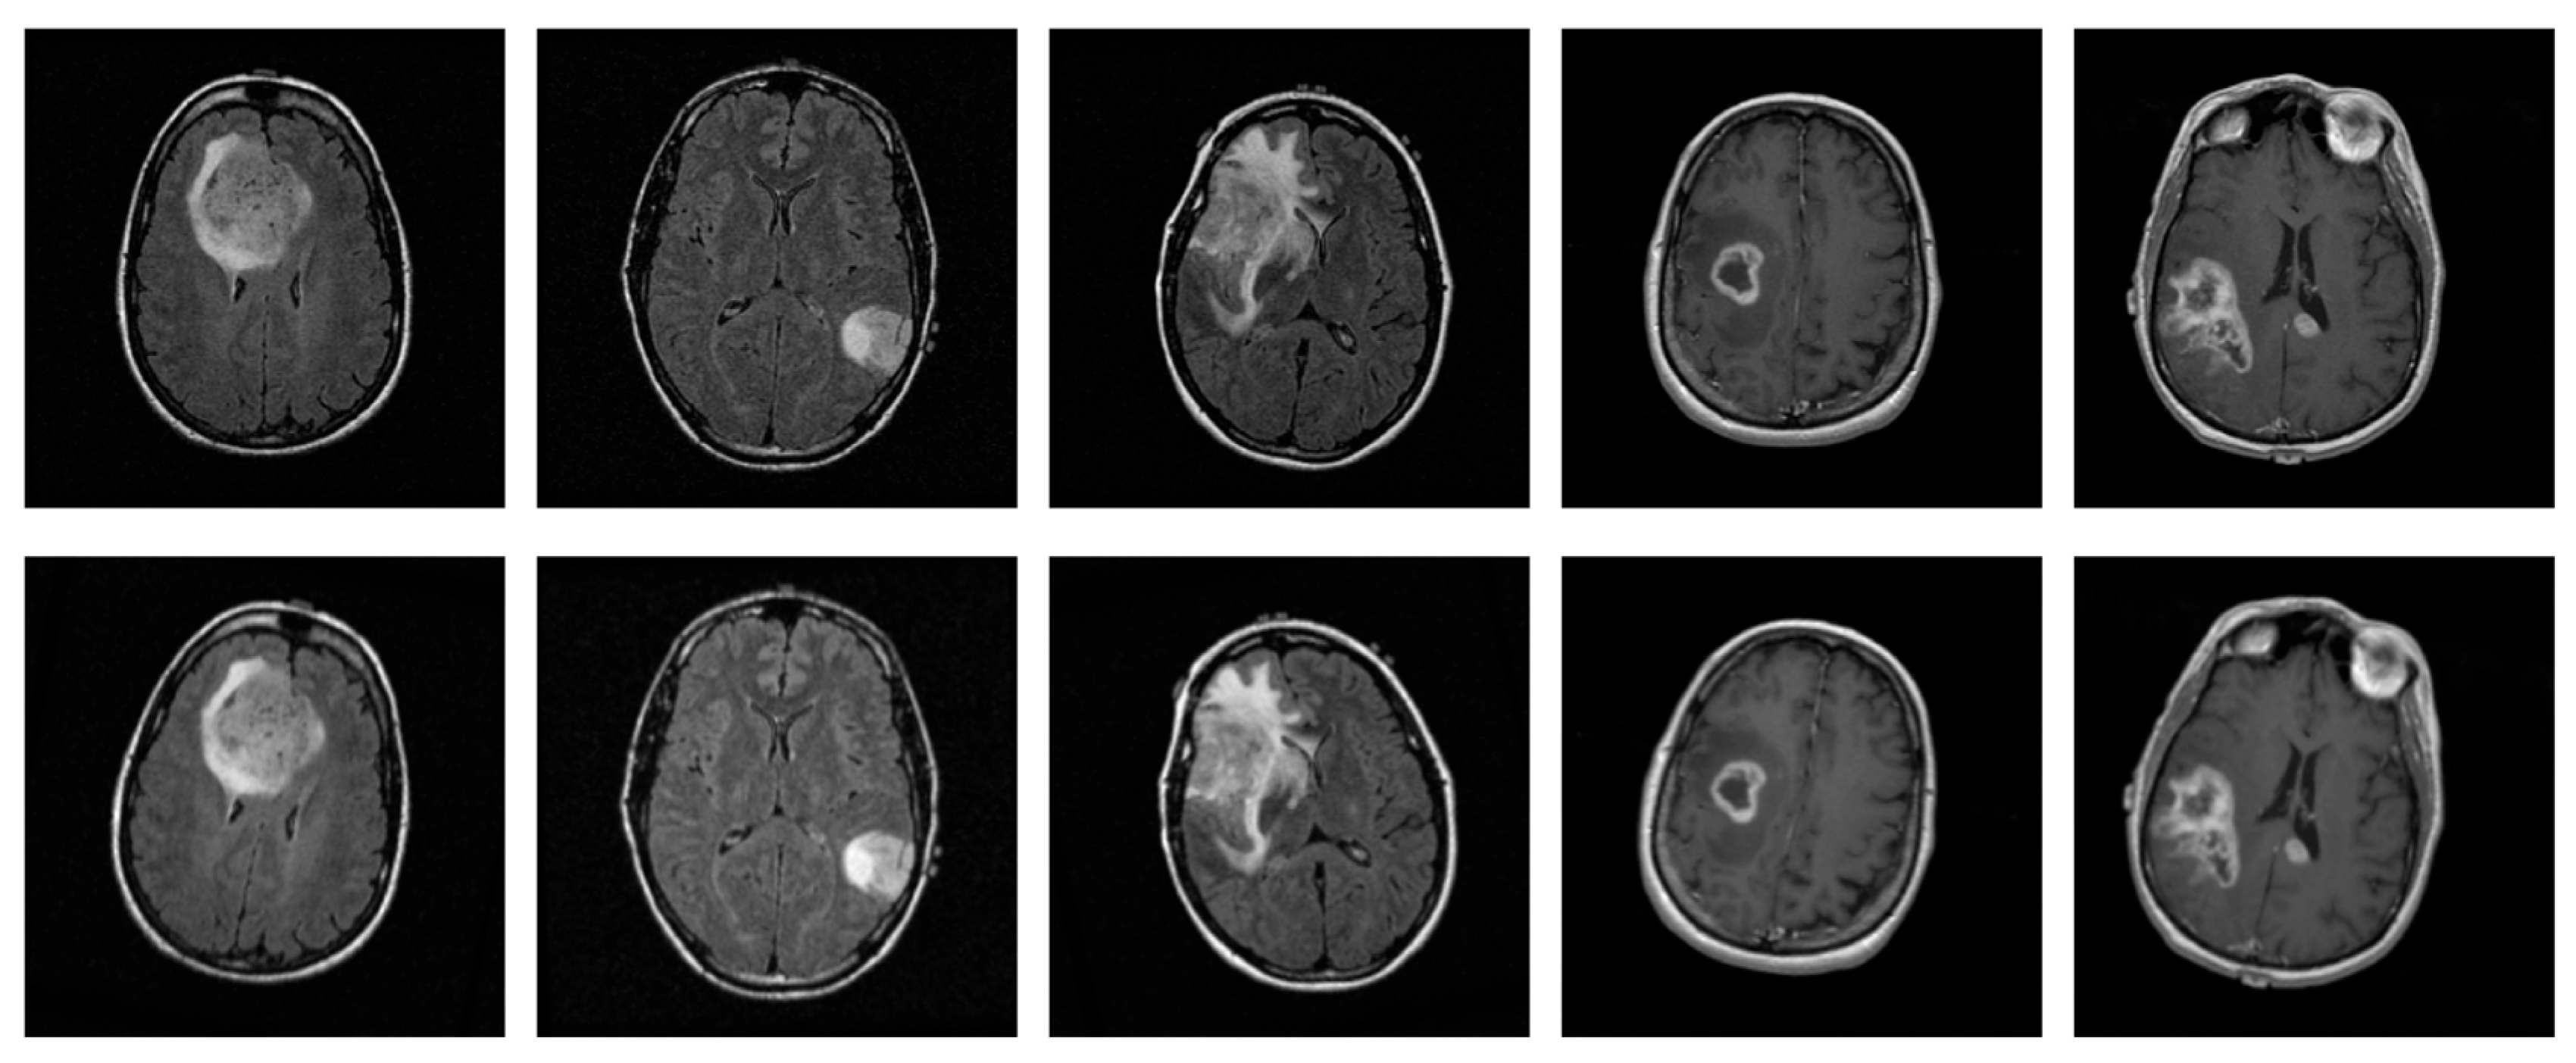

2.1. Data Collection

2.2. Data Pre-Processing